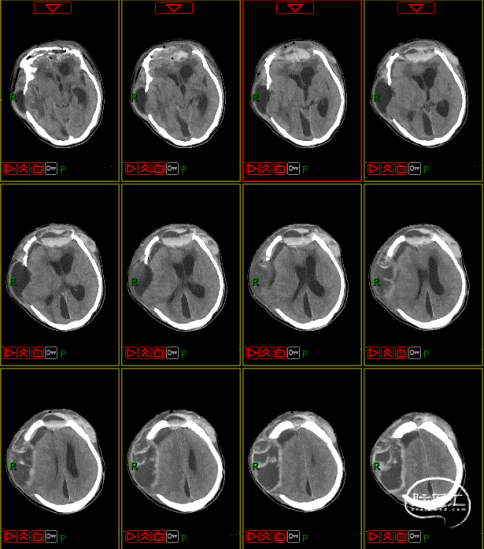

脑积水的处置

第四阶段(多科室康复治疗)

1月28日至7月1日多个科室行康复治疗,3月26日癫痫发作一次。

第五阶段(颅骨修补术)

7月16日行PEEK材料颅骨缺损修补术。